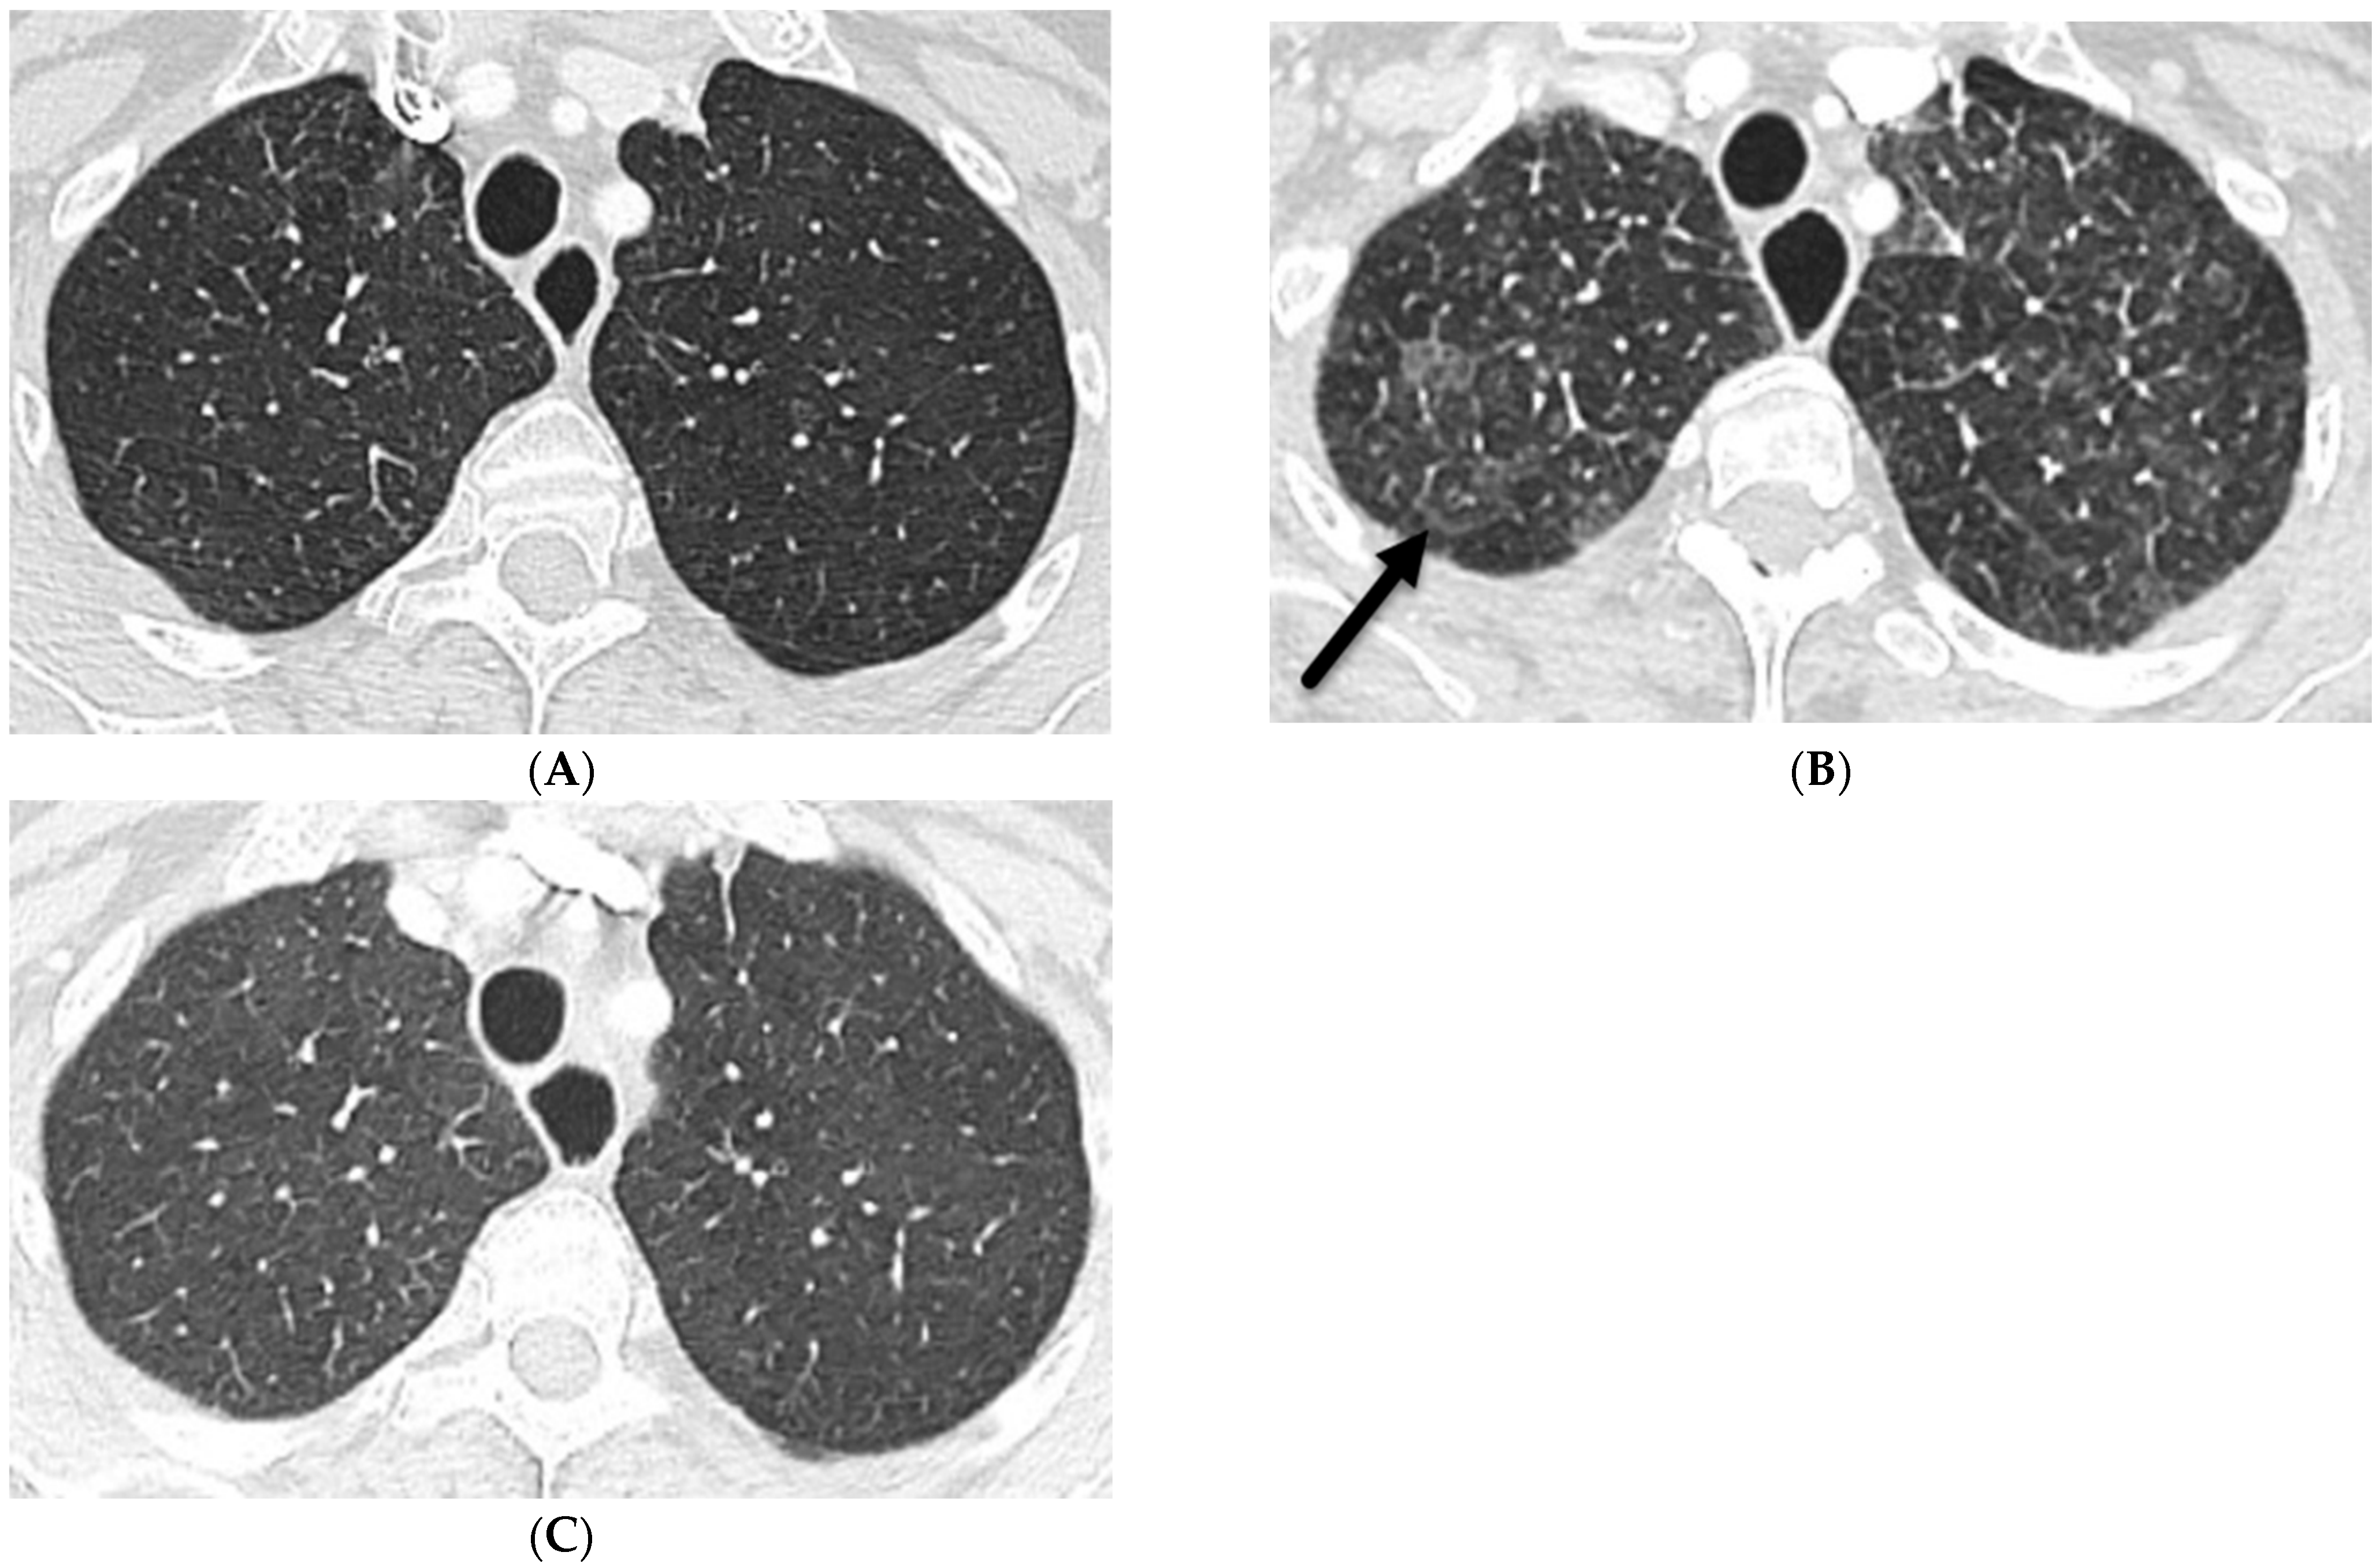

8.2. Granulomatous–Lymphocytic Interstitial Lung Disease (GLILD)

7.6. Pulmonary Hyalinizing Granuloma (PHG)

7.7. Coatomer Subunit Alpha (COPA) Syndrome